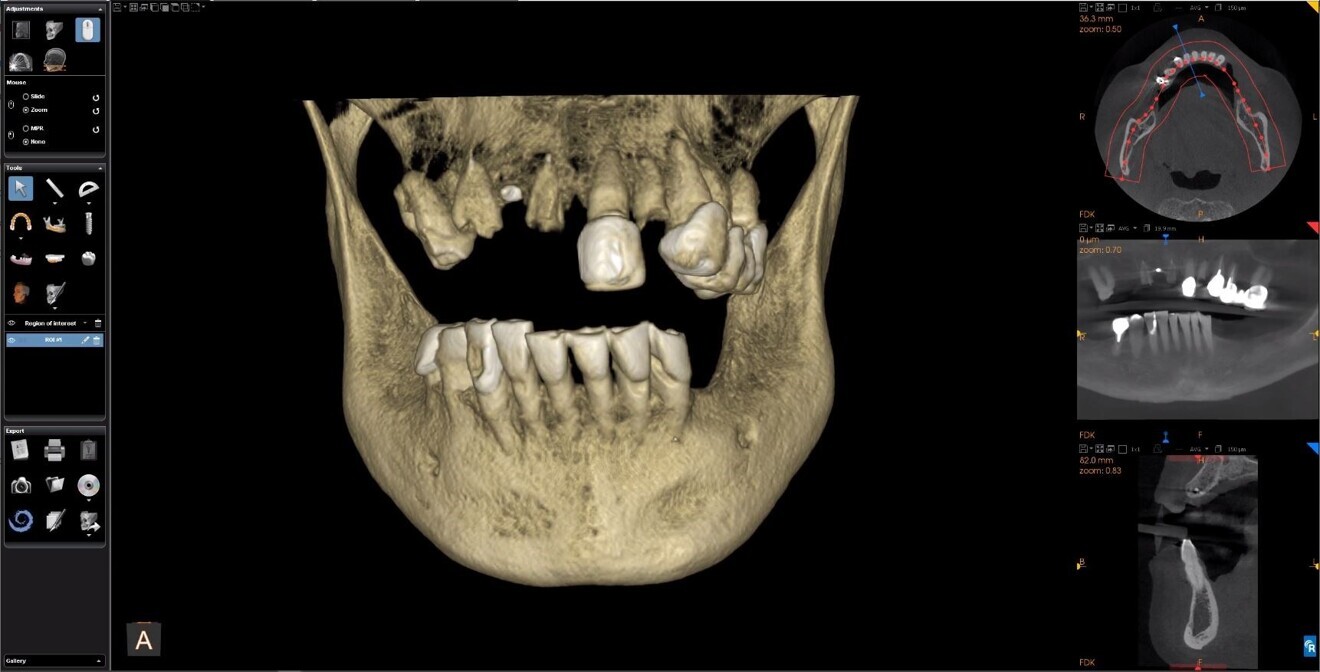

The planning continued with the examination and manipulation of the 3D reconstructed volume of the mandible and maxilla (Fig. 6a). Using the isolate function within the Blue Sky Plan software, the mandibular arch was separated from the maxillary arch, which with the merging of the intra-oral scanning data helped with the restoratively driven planning and refinement of implant positioning (Figs. 6b & c). The implants were then planned with precise regard for the emergence of the screw access channels represented by the yellow abutment projections which extended above the occlusal plane (Fig. 6d). Once each of the implant receptor sites and the vertical positions had been validated, the amount of alveolar reduction (after tooth extraction) was determined. A bone reduction guide was then designed with four anchor pins for stable fixation to the mandible (Fig. 7a). The various components of the diagnostic progress can be better appreciated using selective transparency to visualise structures based on their density (Fig. 7b). Selective transparency was again utilised to visualise the final location of the three central straight implants and the two angled implants, clearly indicating the safe proximity to the bilateral inferior alveolar nerves (Fig. 8a). The translucent STL model of the mandibular teeth and virtual teeth helped relate the implant positions to the restorative plan (Fig. 8b). The sequential osteotomy drilling guide was designed based upon the parameters of the implant system and guided drilling kit utilised. The osteotomy drilling guide was to be secured to the mandible with the same fixation pins as used for the bone reduction guide (Fig. 9).

Fig. 6a: 3D volumetric reconstruction of the maxilla and mandible.

Fig. 6b: The isolated mandibular arch.

Fig. 6c: STL surface model merged with DICOM data with virtual posterior teeth.